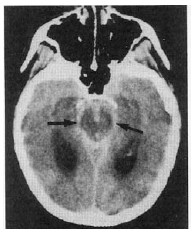

Com relação à imagem mostrada na figura acima, julgue os itens que se seguem.

O local e a extensão da lesão sugerem que se trata de hemorragia subaracnóidea por ruptura de aneurisma sacular, a qual compromete a drenagem liquórica.

Embora a hipertensão arterial (HTA) aumente o risco de repetição da hemorragia intracerebral, o tratamento da HTA é assunto controvertido na presença de hemorragia intracerebral aguda. A tendência atual é tratar-se o paciente quando a pressão sistólica ultrapassar 180 mmHg.

A punção lombar é um complemento necessário ao diagnóstico etiológico desse paciente.

Com base nessa imagem, é correto afirmar que não houve vasoespamo.

A in c idência de aneurismas na circulação posterior é de apenas 4%.